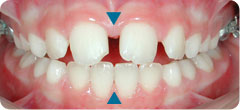

Case: The lower midline is deviated to left because of mandibular shift (see the blue triangles). Lower jaw is forced to grow asymmetrically, to the left.